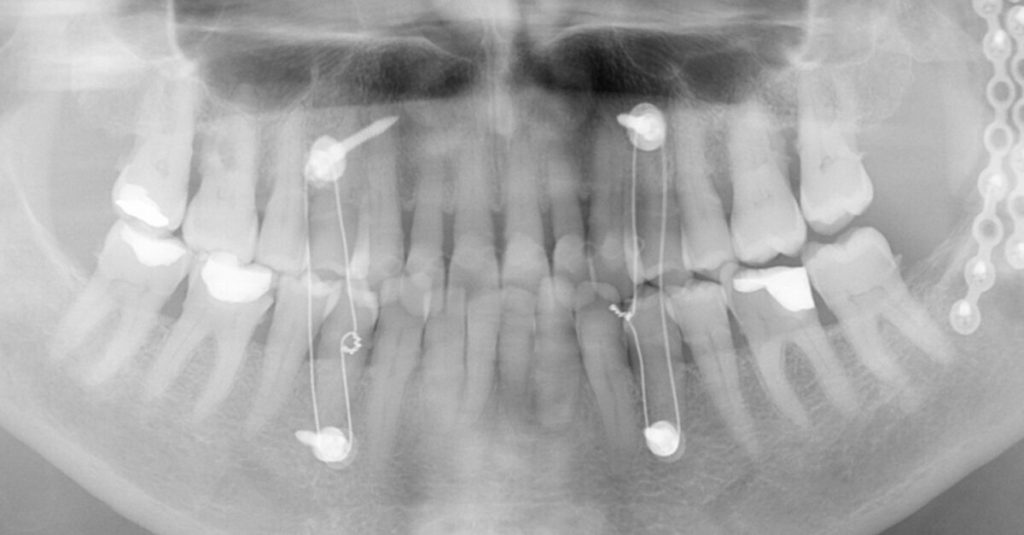

The 85-year-old female patient presented after osteosynthesis of multiple mandibular fractures she had sustained in a fall (Figs. 1 & 2). During fixation, the left posterior region of the mandible was moved such that teeth #34–37 were brought out of occlusion (Fig. 3). The patient naturally wished to be able to chew properly again in this area. After […]